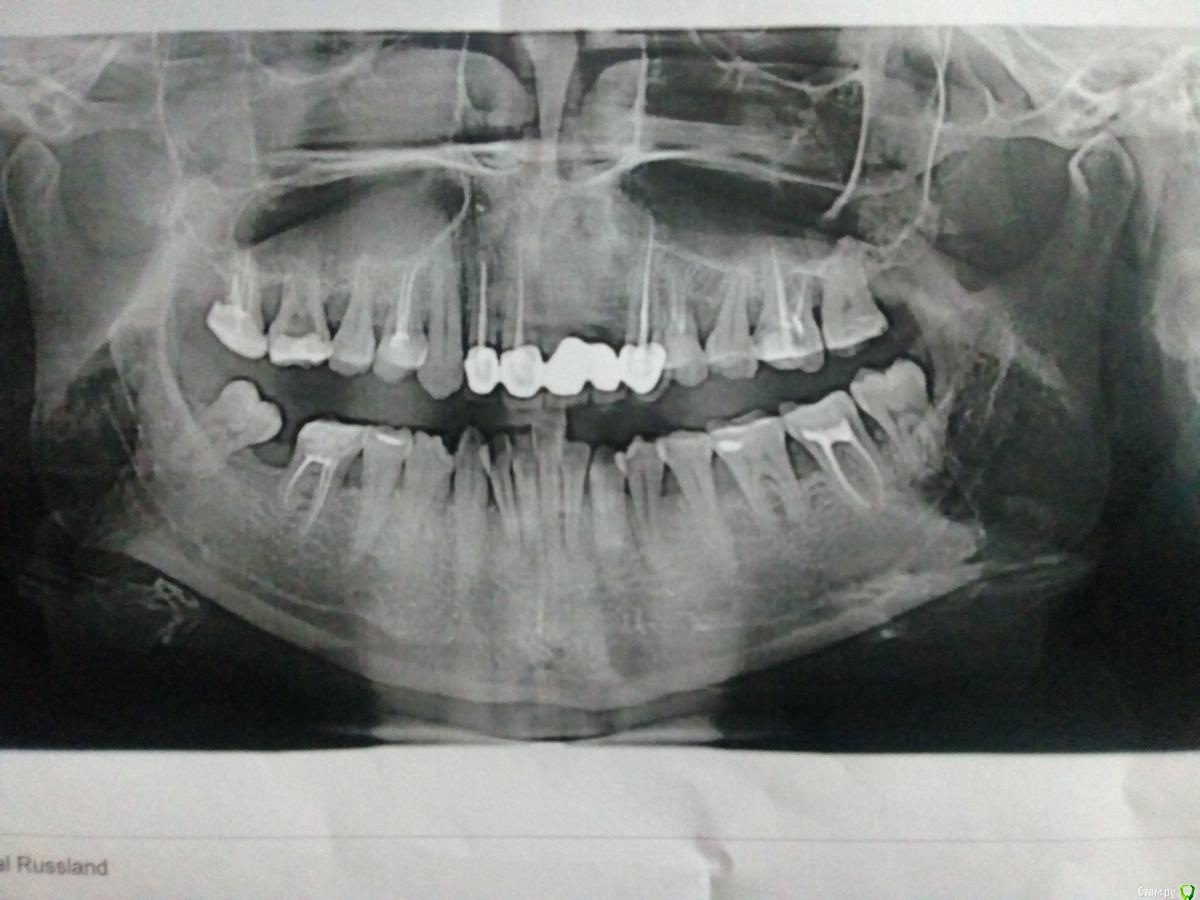

Olga789 Опубликовано 23 июля, 2018 Поделиться Опубликовано 23 июля, 2018 Здравствуйте. Всегда конкретно следила за гигиеной полости рта, но на одном из последних визитов мне сказали, что нужна чистка и консультация пародонтолога. Сделали чистку, посетила пародонтолога. Она поставила диагноз: пародонтит средней степени, выписала два антибиотика: аугментин и орнидозол, также мазь, хлоргексидин и массаж десны. Подвижность зубов по моему мнению отсутствует, после чистки ультразвуком пропала кровоточивость. Скоро снова на прием. Доктор видит два варианта: лоскутная операция или открытый кюретаж. Имеется хроническое заболевание ВСД+тахикардия.Прилагаю снимок. Два передних зуба отсутствуют т.к. при лечении был проперфорирован канал, было воспаление и корень соседнего зуба исчез (со слов врача). Также имеется скученность зубов (на верхней челюсти спереди тоже была). На нижней челюсти зуб был удален по глупости. Вопрос мой к вам такой: целесообразно ли по вашему мнению делать открытый кюретаж (или лоскутную) в моем случае? У моего отца после 40 лет оголились корни зубов, расшатались и выпали. Видимо меня ждет тоже самое, но визуально пока десна не оголилась нигде. Спасибо. Ссылка на комментарий

колесников Опубликовано 24 июля, 2018 Поделиться Опубликовано 24 июля, 2018 (изменено) Судя по костным пикам острая фаза была давно,сейчас ремиссия. Сохраняется локальный острый процесс в области 16-15,26-27.Пользуйтесь ирригатором направляя непосредственно в межзубные промежутки и карманы вертикально. Постепенно десна подтянется до уровня кости. Конечно шейки оголятся и чувствительность появится,тогда и можно будет рассматривать десневую пластику. Изменено 24 июля, 2018 пользователем колесников Ссылка на комментарий